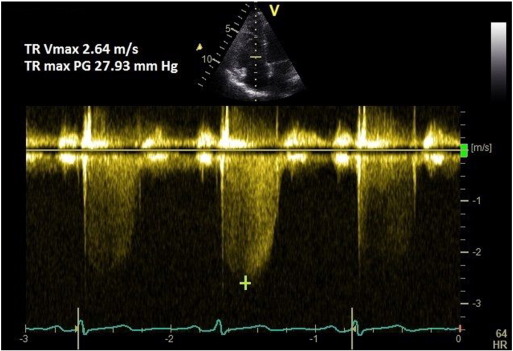

1. Pulmonary artery systolic pressure by TR peak velocity

Continuous wave (CW) Doppler of the tricuspid regurgitation (TR) trace is used to measure the difference in pressures between the right ventricle and right atrium. The simplified Bernoulli equation (P = 4[TRmax]2 ) is used to calculate this pressure difference using peak TR velocity. This method correlates well with PASP on right heart catheterisation [6]  and [7] . A peak TR velocity value of ≤ 2.8 m/s is considered normal.

1.1. Method

A coaxial TR jet is identified in parasternal long axis (RV inflow), parasternal short axis, or apical 4-chamber view with the help of colour Doppler. CW Doppler is used with a sweep speed of 100 mm/s to achieve a satisfactory envelope (Fig. 1 ). The peak velocity of the envelope is then measured (TRmax ). A value of ≤ 2.8 m/s suggests low probability, a value of 2.9–3.4 m/s indicates intermediate probability, and a value > 3.4 m/s suggests a high probability for pulmonary hypertension [1] . Traditionally, right atrial pressure (RAP) is assumed by the size and distensibility of inferior vena cava (IVC) during inspiration at rest and during forced inhalation, and this value is added to the peak TR velocity [8] . However, recent ESC guidelines suggest just using the TRmax without additional RAP, as IVC assessment is error prone [1] . Mean PAP can be approximated from the systolic PAP (SPAP) using the following formula: mPAP = 0.61*SPAP + 2 mmHg [9] .

Fig. 1

Fig. 1.

TR Vmax method for measuring PASP.

If there is marked sinus arrhythmia, the trace should be obtained at expiratory apnoea. If the patient is in atrial fibrillation, then 8 consecutive TR velocities are averaged to give the best estimate [7] . In case of pulmonary valve or right ventricular outflow tract (RVOT) stenosis, this method overestimates the PASP; then the peak pressure gradient across the valve or RVOT should be subtracted from the measured PASP.